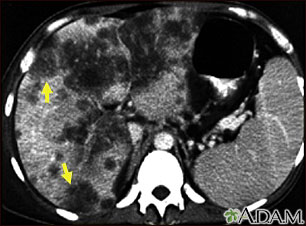

Tomografía computarizada de cáncer hepatocelular

Cáncer hepatocelular, TC

Una tomografía computarizada de la parte superior del abdomen que muestra un carcinoma diseminado del hígado (carcinoma hepatocelular). El hígado es el órgano grande al lado izquierdo de la imagen y presenta una apariencia de haber sido devorado por polillas.